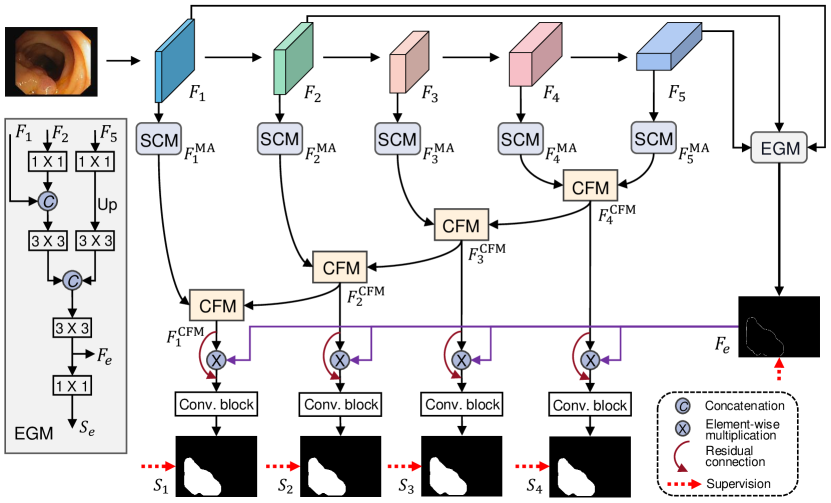

Fig. 2 presents the architecture of our EFA-Net. Specifically, the Res2Net pami20Res2net is adopted as the backbone to extract multi-level features for given images, denoted as . Then, the proposed EGM combines the low-level features (i.e., and ) and the high-level feature (i.e., ) to learn an edge-enhanced feature, which is further incorporated into the decoder. Besides, each feature is fed into the proposed SCM to extract the multi-scale features. Further, we utilize the CFM to integrate the cross-level features to fully exploit the local and global contextual information. Finally, our decoder produces multiple side-out segmentation maps .

Some existing works have pointed out that edge information is able to benefit the segmentation and detection performance fan2020inf ; sun2022boundary ; zhang2019net ; zhao2019egnet . Since low-level features preserve sufficient boundary details, existing methods fan2020inf ; zhang2019net ; zhao2019egnet usually integrate low-level features to learn edge-enhanced representations. Although low-level features contribute more information to learning edge-aware features, they could introduce non-edge coarse details. Therefore, inspired by sun2022boundary , we combine the two low-level features (i.e., and ) with the high-level feature (i.e., ) to construct our EGM. Specifically, as presented in Fig. 2, and are first fed two convolutional layers, respectively, to obtain and . Then, and are cascaded and then passed through a sequential operation to obtain , where is a sequential operation that consists of a convolutional layer, batch normalization and a ReLU activation. Moreover, we conduct a concatenation operation on and to obtain the edge-enhanced feature, which can be depicted by

where denotes an upsampling operation. Finally, is passed through a convolutional layer to generate an edge map (), and the edge map is upsampled to ensure that it has the same resolution as the original image. Here we adopt the binary cross-entropy (BCE) loss (termed ) to measure the difference between the produced edge map and ground-truth map (, which is obtained by using the Sobel detection operator), and the associated loss can be defined by . Note that, provides an edge-aware feature to weigh the features in the decoder for boosting the segmentation performance.

where denotes an element-wise addition operation. As a result, we obtain the scale-aware feature , which is regarded as the output of the -th SCM.

3.4 Cross-level Fusion Module

where denotes element-wise multiplication. After that, the two attention-enhanced features and the original feature are concatenated and then fed to a sequential convolution operation to generate the final output , which is obtained as follows:

| (6) |

Model Inference: We have obtained the cross-level fused features , thus it is important to integrate the edge-aware feature to provide more boundary details. To achieve this integration, the edge-aware feature is first passed through a Sigmoid activation to normalize values to , which can be used as an edge feature-level attention map. In order to preserve the original information from , a residual connection strategy is also adopted to combine the edge-enhanced feature with , thus obtaining the edge-aware features

Then, will pass through a “Conv. block” (as shown in Fig. 2) to produce multiple side-output segmentation maps, namely . Here “Conv. block” contains two sequential convolutions (i.e., ) followed by a convolution.